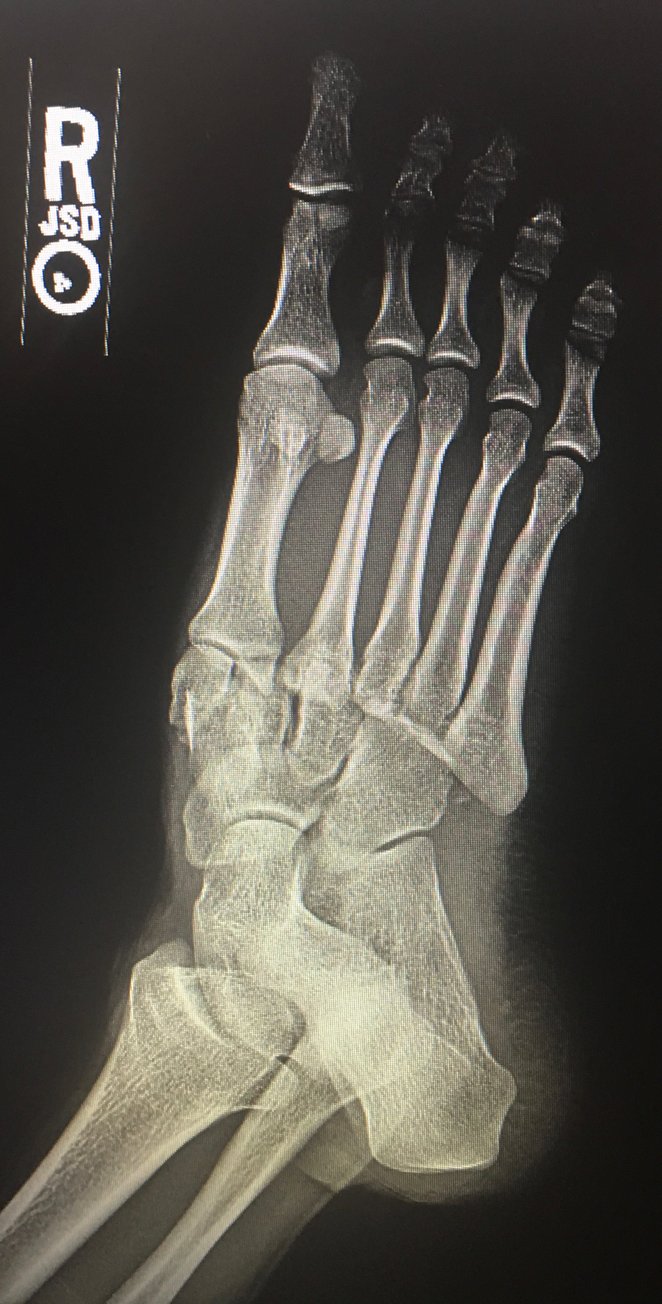

The frontal view of the right foot showed divergent dislocation of the second through fifth metatarsal bones (red outlines) consistent with Lisfranc injury. Though the Lisfranc ligament is not visualized by radiograph, the yellow markings represent the location of the Lisfranc ligament between the medial cuneiform (blue dot) and the base of the second metatarsal bone. The first metatarsal and the medial cuneiform remain congruent. The lateral view shows dorsal dislocation of the midfoot (pink circle) consistent with instability. There is associated extensive midfoot soft tissue swelling.